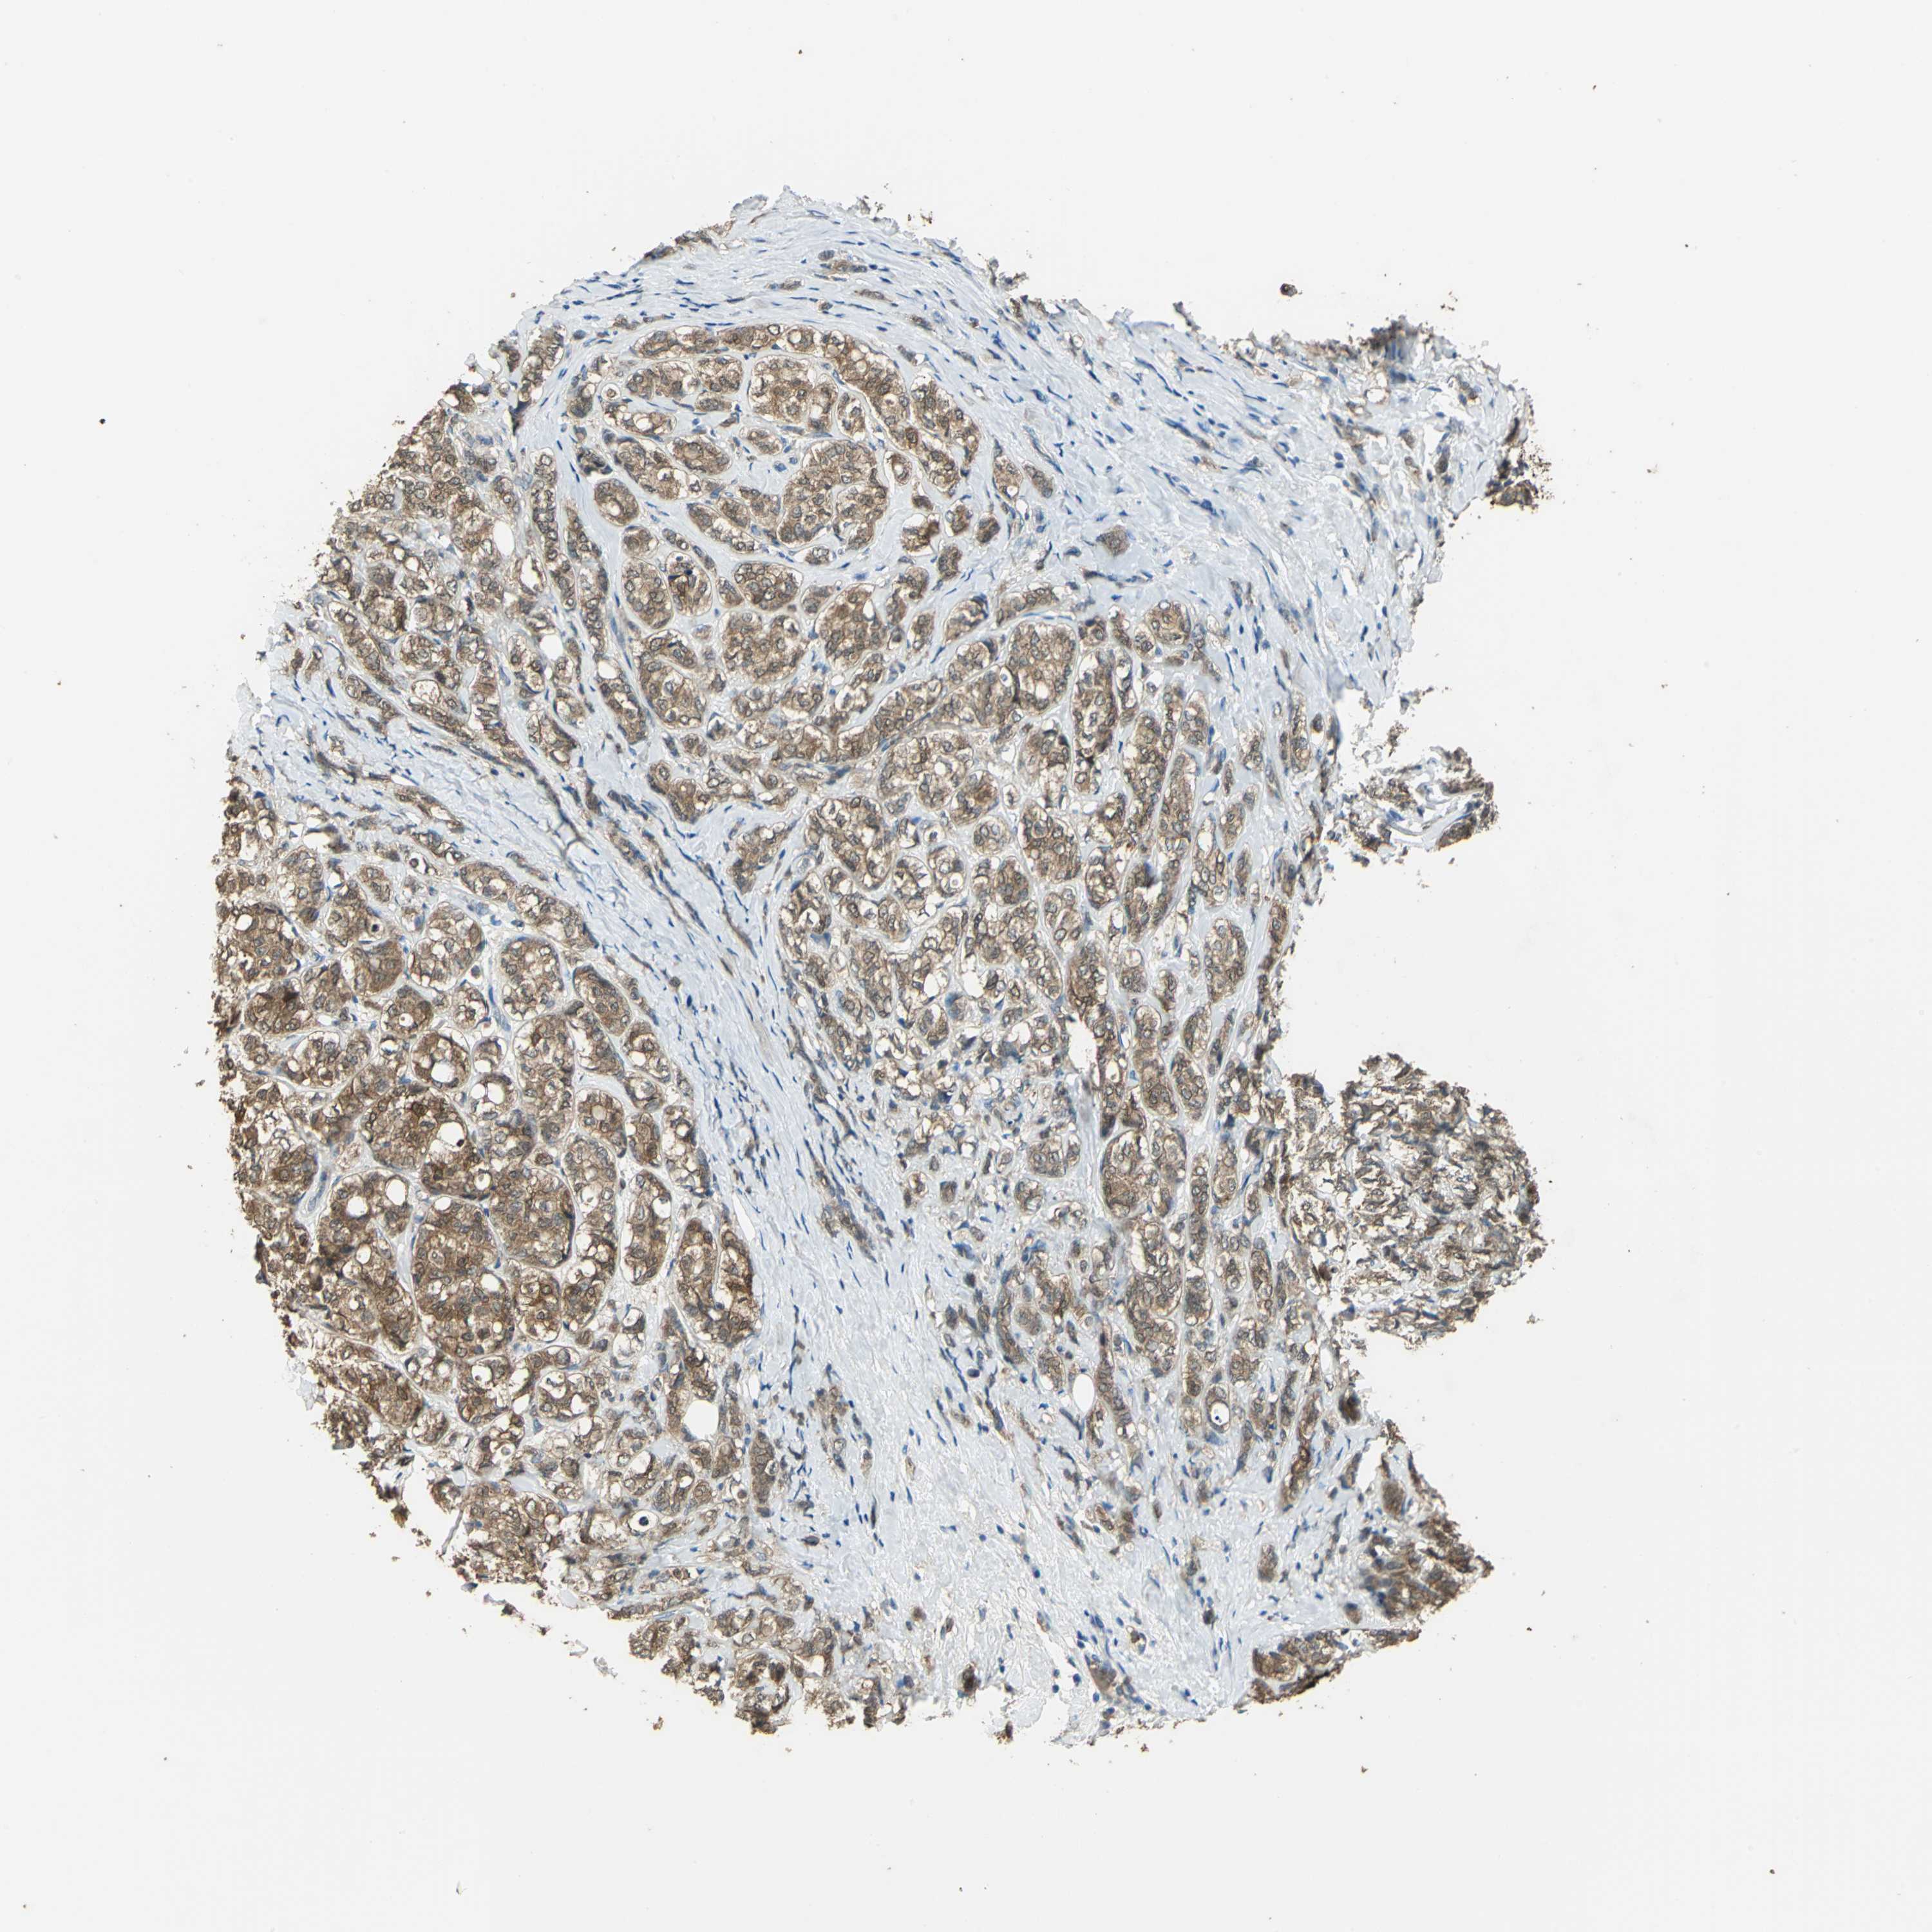

CANCER BREAST CANCER Show tissue menu

BRCA TCGA BRCA VALIDATION PROTEIN EXPRESSION